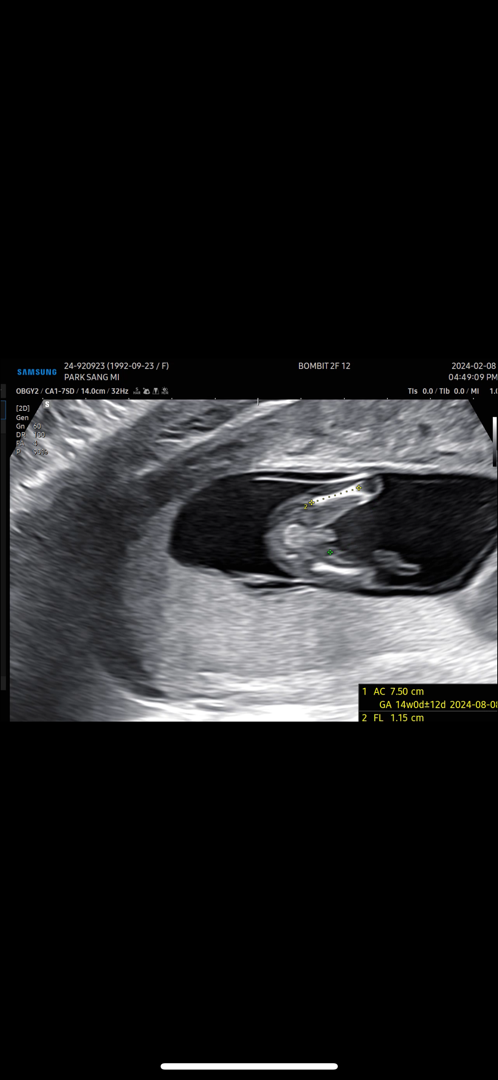

13주 이정도면 성별 변할 가능성 없겠죠..?

13주 3일인데요~ 허벅지 뼈길이 재주시다가 도저히 못본척 못하시겠다고...ㅎㅎ 이정도면 바뀔 가능성은 없겠죠??ㅋㅋㅋ...

앗 그런가요ㅎㅎ! 안양 봄빛병원입니다

저두 어제 확인했구 14주인데 ㅋㅋ비슷해요 존재감이 뿜뿜하더라구여 아들은🤣🤣

저도 네이버 아무리 검색해도 이렇게 적나라한 고츄는 처음이라......ㅋㅋㅋ 이게 맞나 해가지고..............ㅌㅋㅋㅋㅋㅋㅋㅋ